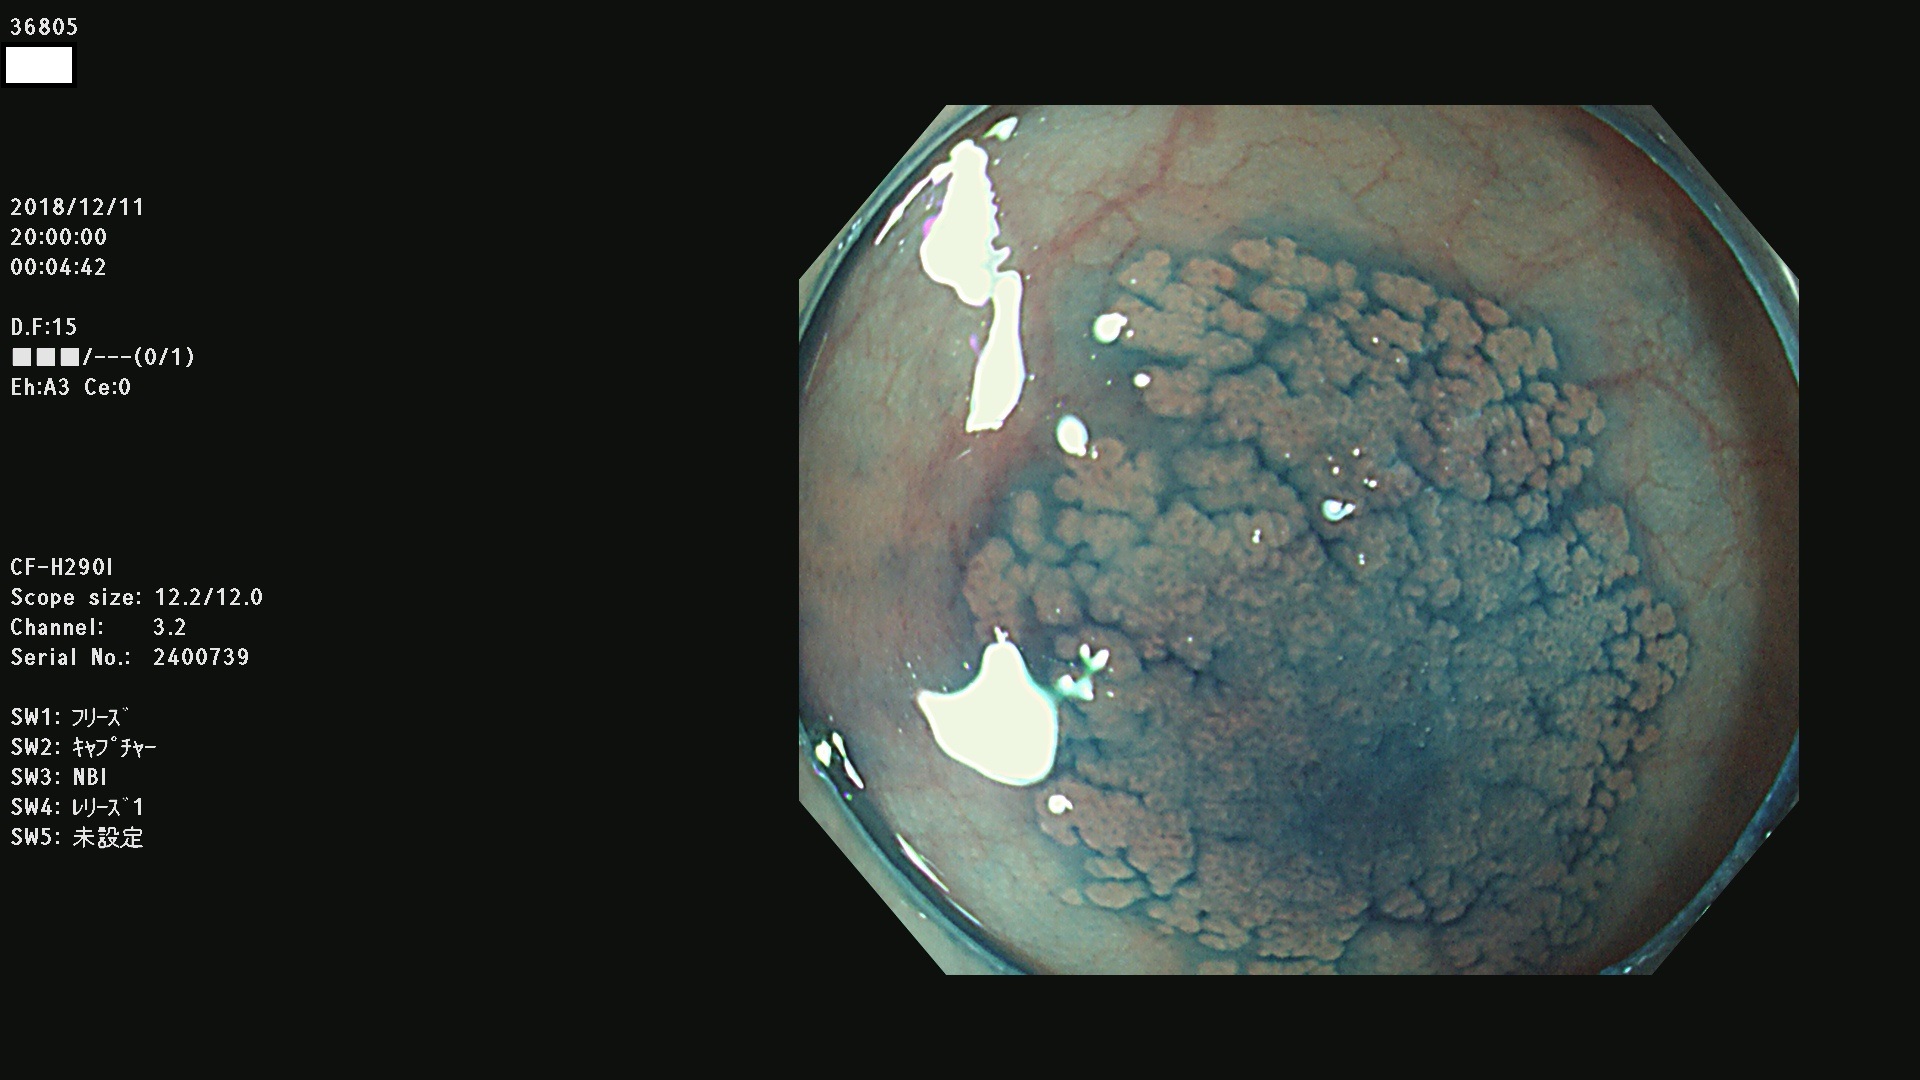

36804 36806 36807 36808 36809 36810 36811 36813 36815 36816 36817 36818 36820 36821 36822 36824 36825 36826 36828 36829 36830 36831 36832 36833 36834 36835 36837 36840 36841 36842 36845 36846 36848 36849 36851 36852 36853 36854 36855 36857 36859 36860 36861 36862(SSAPのみ) 36863 36864 36866 36868 36869 36870 36873 36875 36877 36878 36879 36881 36882 36883 36884 36885 36886 36887 36888 36889 36891 36892 36893 36894 36895 36896 36897 36898 36899

発見困難で危険性の高い平坦型病変(上記100名より抽出)